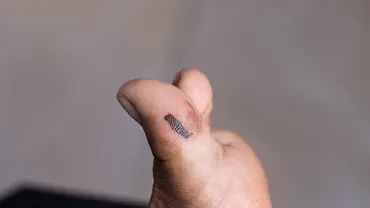

Artikelbild und Social Media: Wittybear/iStock (Symbolbild)